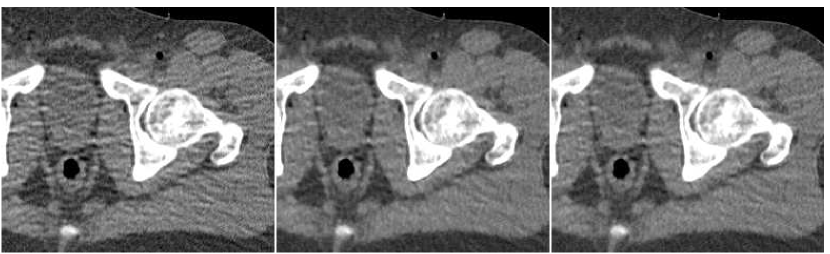

In Figure 6 we present a reconstruction of a test image. This test image is taken cm away from the region where the training data was taken from. The middle upper image is the result of a fusion of the number of FBP versions, performed with the trained ANN. By the visual impression, the noise-resolution balance in the fused image is better than in any of the FBP versions forming it. The texture of tissues is closer to the original (observed in the reference image, upper left). The level of streaks and general noise are lower than in the central and right FBP images, and the image sharpness is higher than in the left and the central images. Thus, the fusion image enjoys the good properties offered by each of the FBP versions and is superior than any of them.

Recall that the training was done with a set of weights, corresponding to our penalty component from Equation IV-C. The quantitative error measures we compute for this comparison include plain SNR, SNR weighted by those weights, the training risk and the SSIM measures. These values are given in Table I. As observed from the table, the weighted SNR of the fusion image is dB higher than the highest attainable value in FBP images. For plain SNR this increment is dB. Values of the training risk measure behave expectedly: the weights of ANN training were designed to implicitly reduce this measure for the fusion image. Indeed, it is by lower than that of the optimal FBP image. Finally, the SSIM measure supports the claim the fusion image has the best visual appearance, since it admits the larger value for this measure.